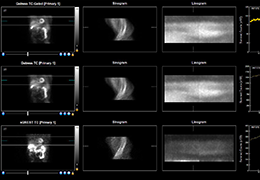

Traditional multi-planar slicing

Multi-planar slicing.

Oblique slicing.